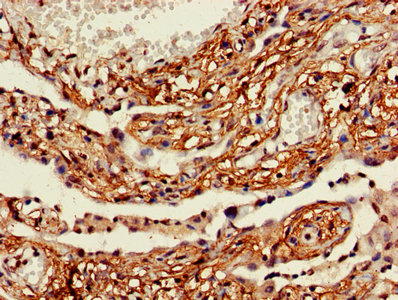

IHC image of CSB-PA891734HA01HU diluted at 1:600 and staining in paraffin-embedded human lung cancer performed on a Leica BondTM system. After dewaxing and hydration, antigen retrieval was mediated by high pressure in a citrate buffer (pH 6.0). Section was blocked with 10% normal goat serum 30min at RT. Then primary antibody (1% BSA) was incubated at 4°C overnight. The primary is detected by a biotinylated secondary antibody and visualized using an HRP conjugated SP system.